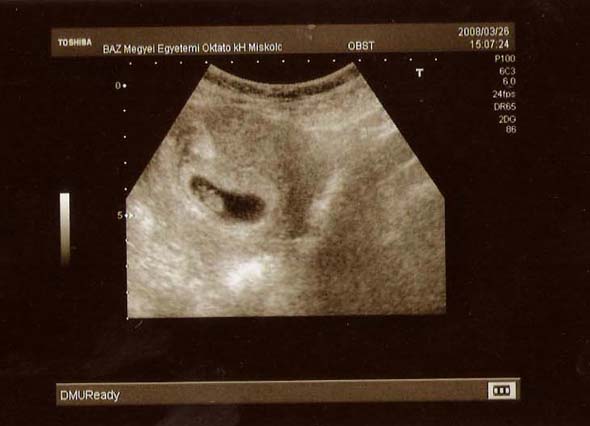

örülök, hogy minden rendben van. Ugye milyen jó a saját picikédet nézegetni azon a képen? Igaz, hogy egy paca az egész, de.... olyan leírhatatlan.